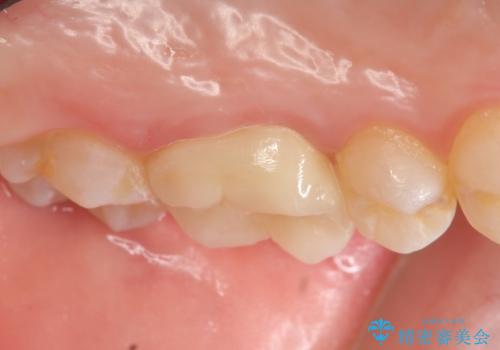

検査の結果左上6に持続痛を認めたため根管治療を行い、症状の緩解を確認後オールセラミッククラウンによる補綴を行いました。

今回用いたオールセラミッククラウンはジルコニアフレームという白い素材の上にセラミックを盛っているため、審美性が非常に高いのが特徴です。

また、ジルコニアは人工ダイヤモンドの材料にも使われているほど高い強度を持っており、そのためオールセラミッククラウンは審美性だけでなく、奥歯やブリッジの補綴も可能とするクラウンです。